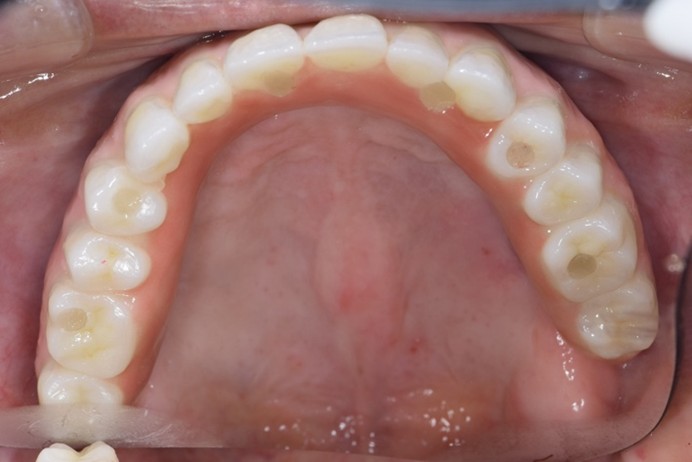

症例1

| 術前 | 術後 |

| ご来院時の主訴 | 入れ歯を入れたが落ちてくる。 インプラントの話を聞いたので入れ歯じゃなくてインプラントをしたい。 |

| 年代・性別 | 70代 女性 |

| 治療部位 | 上顎7〜7 |

| 治療費用 | 2,420,000円 |

| 手術回数 | 2回 |

| 治療期間 | 25か月 |

| 手術時間 | 90分×2回 |

| 治療回数 | 28回 |